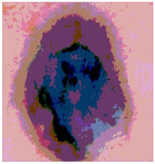

| Segmented Image | R | G | B |

|---|---|---|---|

![]() | ![]() | ![]() | ![]() |